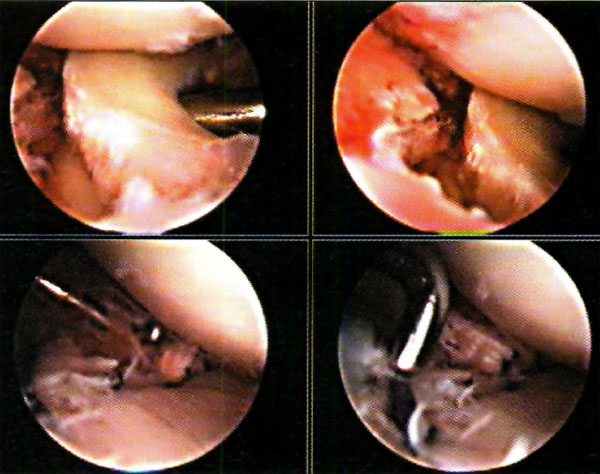

En las lesiones meniscales realizamos su sutura si la lesión es periférica (Fotos 1) o la menisectomía parcial si no reuniera condiciones de sutura. Las lesiones osteocondrales son tratadas con técnicas de estimulación mesenquimática, y en las lesiones de ligamentos cruzados, diferimos eventualmente su reconstrucción para un segundo tiempo quirúrgico. Luego de reconocer el trazo de fractura (localización, dimensiones, conminución, desplazamiento de los fragmentos, etc.) procedemos a su tratamiento. En las fracturas por hundimiento, realizamos una ventana ósea a nivel metafisodiafisario (aproximadamente 8 cm. por debajo de la línea articular ipsilateral a la fractura) a través de la cual introducimos un impactor romo (doble acodado a 90°), y procedemos a reducir los fragmentos hundidos mediante suaves golpes bajo visión artroscópica. (No utilizamos la guía tibial de ligamento cruzado anterior para ubicar la zona de lesión, dado que nuestros impactores son acodados y no canulados.)

Foto 1: Sutura meniscal

Los reparos utilizados para la reducción de la meseta tibial son el borde sano del cartílago y la cara inferior y el borde libre del menisco.(Fotos 2)

A medida que se corrige el hundimiento, controlamos mediante artroscopía si algún fragmento óseo se hipercorrige, reduciéndolo con el palpador o una cureta. (Fotos 3, 4, y 5 )